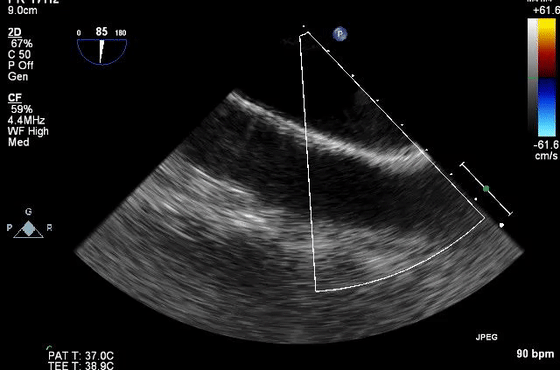

10、经食管超声图像伪像

虽然上面介绍的主要集中在常规经胸超声心动图,但上述伪像也经常在经食管超声心动图中遇到。图10显示了经食管超声心动图中一些常见的伪像。在这方面最相关的临床情况是(1)排除LAA中的血栓(图10E和10F)和(2)排除主动脉夹层(图10G和10H)。